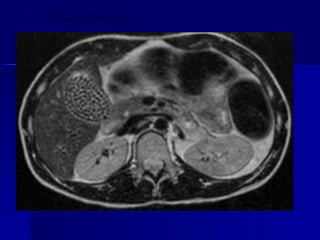

COLELITIASIS –  RESONANCIA MAGNÉTICA